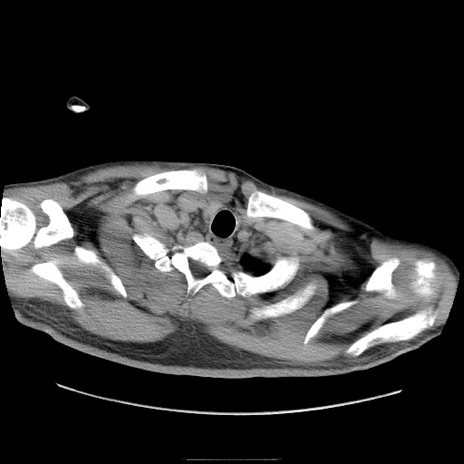

冠状断像

【症例】50歳代男性

【主訴】腹痛

【現病歴】AVMからの被殻出血のため回復期リハ病棟入院中。 本日午後3時頃急に下腹部痛が出現した。

【既往歴】AVM、被殻出血、虫垂炎、高血圧

【身体所見】意識晴明、左半身不全麻痺、会話の理解は良好、36.5°C、腹部:膨隆、全体に板状硬、下腹部正中に圧痛点あり、反跳痛-、筋性防御不明、右下腹部にope scar

【データ】WBC 9400、CRP 0.06